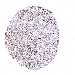

PANCREATIC CANCER - Protein expressioni

A mouse-over function shows sample information and annotation data. Click on an image to view it in a full screen mode. Samples can be filtered based on level of antibody staining by selecting one or several of the following categories: high, medium, low and not detected. The assay and annotation is described here.

Note that samples used for immunohistochemistry by the Human Protein Atlas do not correspond to samples in the TCGA dataset.

Antibody stainingi

Antibody staining in the annotated cell types in the current human tissue is reported as not detected, low, medium, or high, based on conventional immunohistochemistry profiling in selected tissues. This score is based on the combination of the staining intensity and fraction of stained cells.

Each image is clickable and will lead to virtual microscopy that enables deeper exploration of all samples and also displays staining intensity scores, fraction scores and subcellular localization as well as patient and tissue information for each sample.

Antibody HPA037866

Antibody HPA037867

Antibody HPA045712

Staining

High

Medium

Low

Not detected

Intensity

Strong

Moderate

Weak

Negative

Quantity

>75%

75%-25%

<25%

None

Location

Nuclear

Cytoplasmic/membranous

Cytoplasmic/membranous,nuclear

Adenocarcinoma, NOS